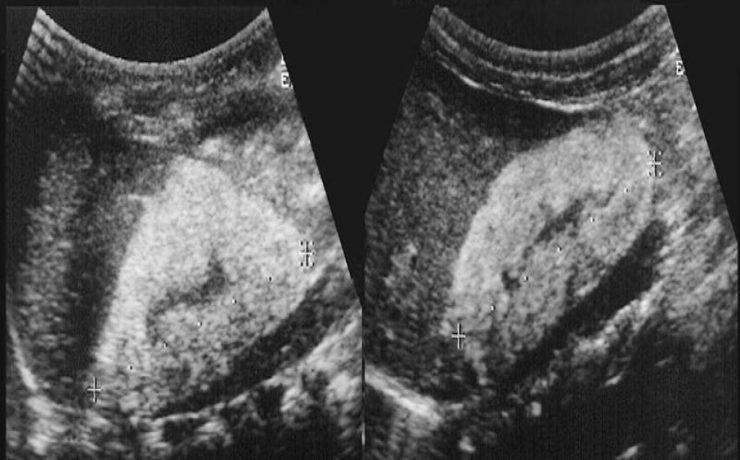

Los bultos o anormalidades en la mama generalmente se detectan por medio de un examen físico, mamografía, u otros estudios de diagnóstico por imágenes. Sin embargo, no siempre es posible detectar a través de dichos diagnósticos por imágenes si el crecimiento de los mismos es cancerígeno o benigno. Una biopsia